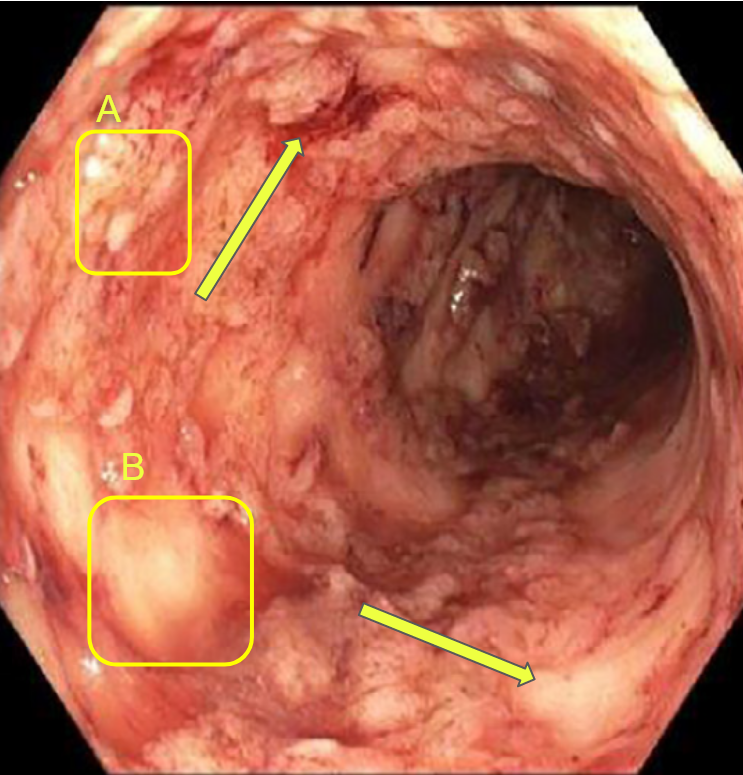

Now let’s move to biology which is the science of living organisms extending from the molecular level to the mesoscopic ecosystems. In this paper, we focus on the modelling of the inflammatory process hitting the bowel. Crohn’s disease and ulcerative colitis are both inflammatory bowel diseases but they are different indeed [15, 16]. Ulcerative colitis (UC) is a chronic inflammatory bowel disease resulting from an overreaction of the natural defenses of the digestive immune system, with an estimated prevalence of 1 in 1500 people with an annual incidence of 6 to 8 new cases per 100,000 inhabitants in Australia [17], Western Europe and the United States. In Tunisia, the incidence is estimated at 2.11 per 100,000 inhabitants per year [18, 19]. UC is not a rare disease in tunisian adults, but in children. It is characterized by smooth ulceration of the inner lining of the colon. The inflammation begins in the lower region of the colon, just above the anus, and progresses upward at varying distances. One of the most important indicators of the severity of this disease is the spatial distribution of the intestinal lesions associated with an introduced gastro-enterologist’s severity score. While individuals with moderate to high severity scores have a concentration of lesions around the rectum, those with low severity scores frequently have a homogeneous spatial distribution of colonic lesions. UC appears in lesions such as bleeding rectal and colon ulcers. It is a currently incurable disease characterized by varying intensities of inflammatory relapse with interspersed remission periods. This puts the patient at higher risk of colon cancer than the general population thus the potential removal of the organ (colectomy). Currently available treatments aim to control pain, reduce the frequency and duration of relapses, and thereby relieve symptoms. Crohn’s disease is a type of painful inflammatory bowel disease (IBD) that is not well understood. In Tunisia, this serious disease affects both children over 10 and adults [18]. It consists of the appearance of several asymmetrical segments of deep lesions separated by intact areas. In the worst cases, these areas can turn into fissures or even holes in the wall of the intestine. Unlike other IBDs, it affects any part of the gastrointestinal tract, from top (the mouth) to bottom (the anus), in contiguous or isolated parts. The inflammation can affect the inner lining and even go beyond the entire thickness of the intestinal wall; It is manifested by a blood vessels dilation and tissues fluid loss. It is usually present in the lower part of the small intestine that connects to the colon. The inflamed portion of the intestine affects the deep panniculus and is not adjacent to it, but rather is distributed throughout the gastrointestinal tract, with an erratic inflammation pattern. The diagnosis of this disease requires advanced technological tools which present difficulties in the collection of data to predict the spread. For that, the mathematical modeling has been increasingly utilized as a tool to understand the complex and dynamic processes involved in both diseases as shown in [5, 20].

Gastro-enterologists and surgeons are hindered from having spatial information on anatomical sites since these indicators are not spatial, and the provided information is never localized in a specific position. The diagnosis of these diseases is based on the analysis of colonoscopy videos. Thus, physicians assess the severity of the disease according to the presence of inflammation, bleeding or ulcers on the intestinal wall which requires an advanced level of expertise. In the same way, the extent of the lesions is currently ignored in medical practice, for lack of a validated method for analyzing this information. This same remark applies to other indicators like numerical score of severity [21], the speed of inflammation propagation, the choice of treatment [22]. Gastroenterologists recognize the significance of spatial information in the development of complications such as esophageal and colon cancer in patients with Crohn’s disease and ulcerative colitis. However, current guidelines fail to fully consider the quantity and distribution of lesions, often focusing solely on the most severe lesion identified. This is due to the scarcity of software tools and scientific literature. Additionally, the intricate feedback loops and technical challenges in collecting high-quality data for the calibration of numerical and mathematical models (see figure 2) further highlights the need for innovative methods. This necessity is the driving force behind our current study, which aims to address the limitations in current approaches and provide a more comprehensive understanding of the disease.

Endoscopic video analysis [24] plays a crucial role in evaluating the severity of ulcerative colitis and monitoring the progression of the disease. Colonoscopy is widely used as the reference examination to assess the intensity of the disease and the extent of intestinal lesions. During this routine procedure, a gastroenterologist inserts a camera-equipped endoscope into the colon to visualize the inner lining and take biopsies if necessary. It should be noted that this technique has a very strong impact on the quality of life of the patients.

Both colonoscopy and WCE allow for the detection of important lesions in the videos, such as: Loss of visibility of the vascular framework, which is indicated by the disappearance of blood vessels and the formation of fibrous tissue that impedes nutrient absorption and inflammation and bleeding, which appear as red areas on the intestinal wall and ulcers and indentations in the wall that appear white or gray. The precise collection and examination of the endoscopic video data is essential not only for identifying the disease presence and advancement, but also for categorizing the different types of IBDs and classifying the subtypes within the same disease.